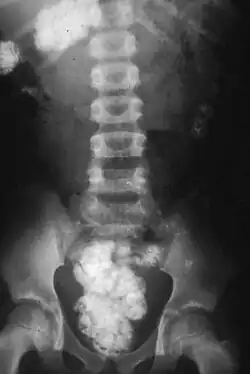

Charakteristisch für den regelmäßigen Erdeesser ist der Hängebauch, allgemeine Abmagerung, Anschwellung der Leber und Milz. Auffällig ist die Häufigkeit leidenschaftlichen Erdeessens im kindlichen Lebensalter.